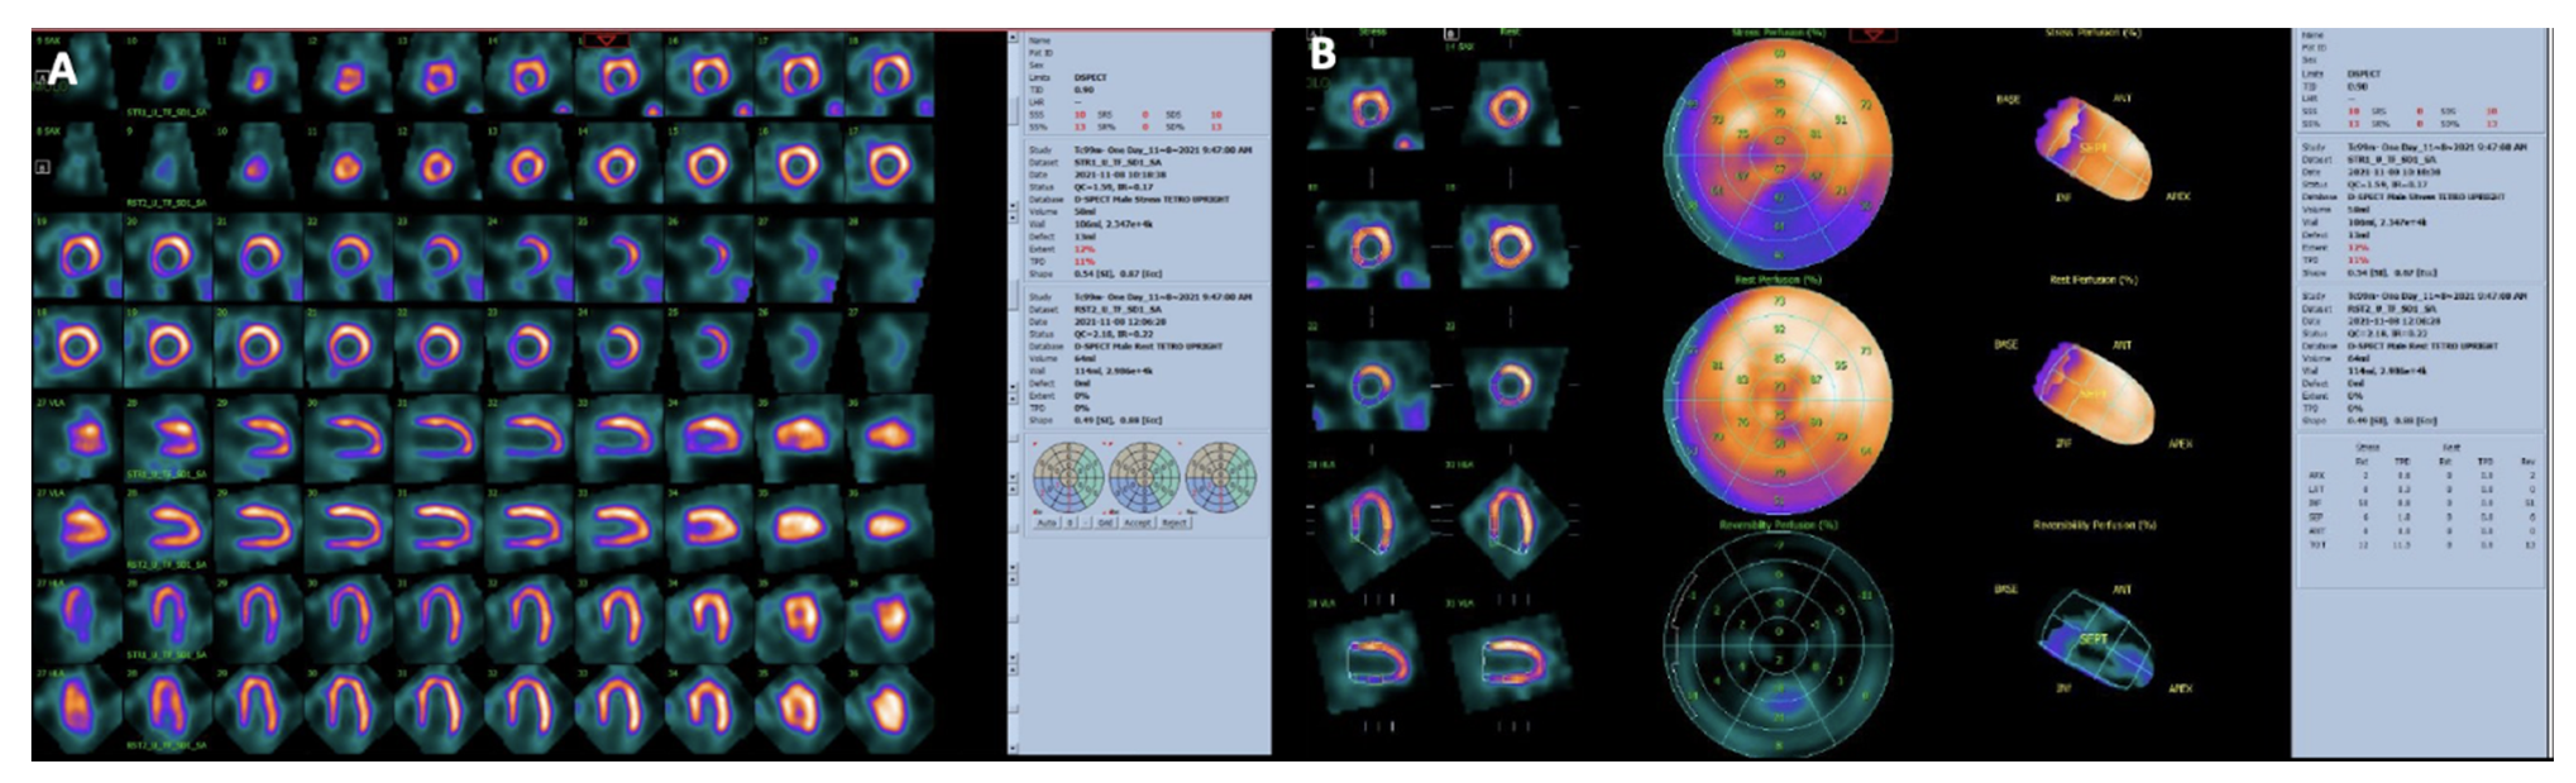

5.1. Myocardial SPECT